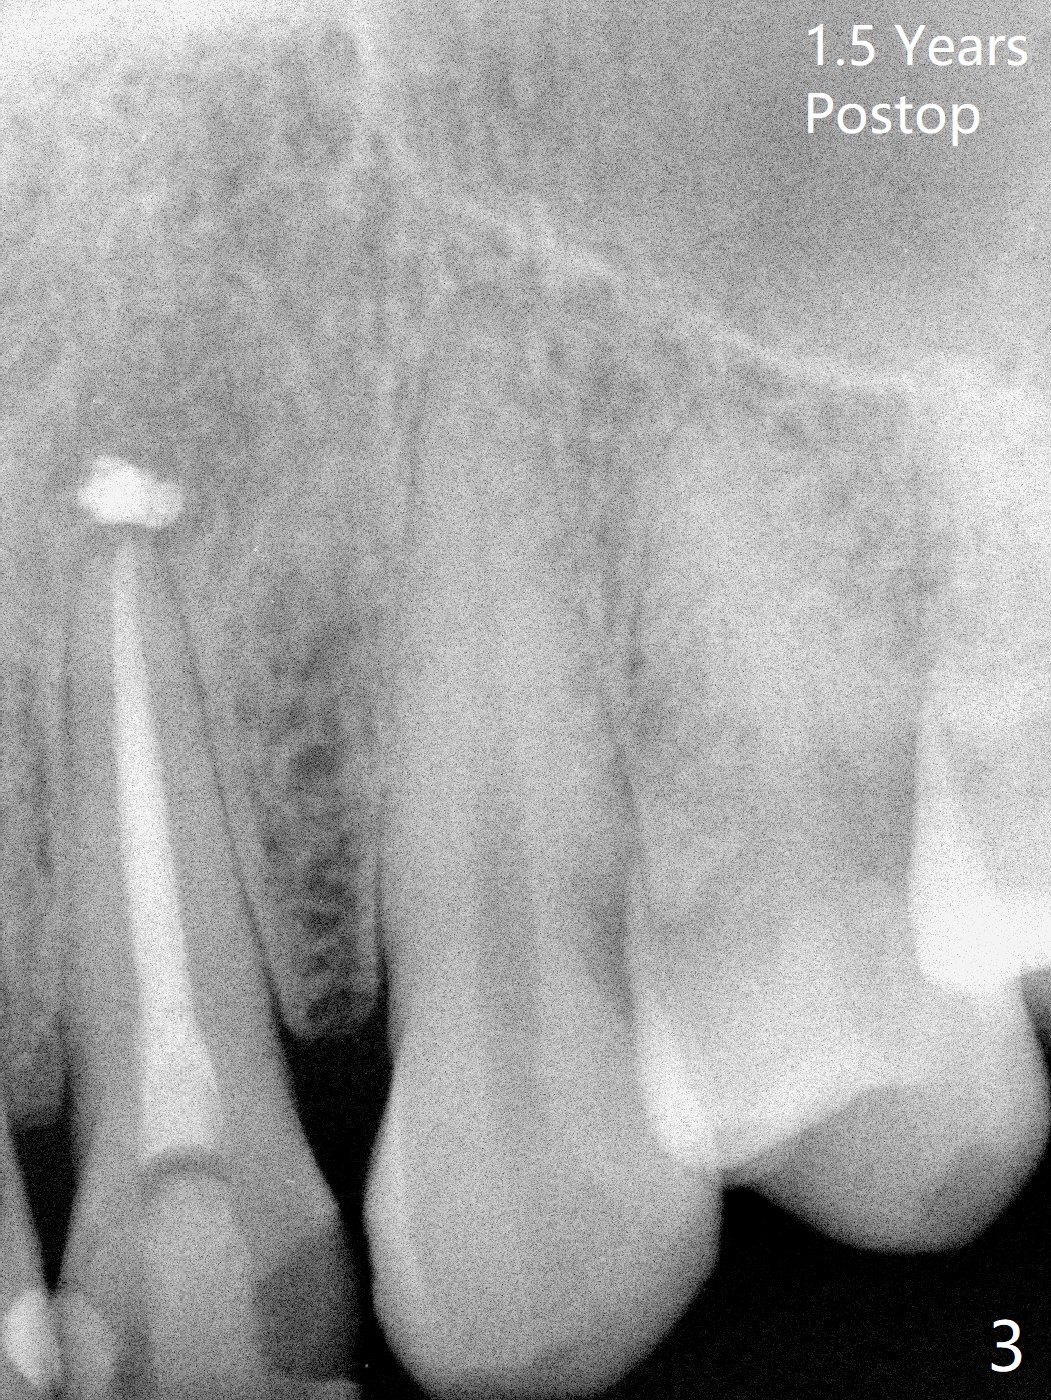

A 47-year-old woman with multiple restoration has PARL at #10 (Fig.1 *). RCT is done with paste leakage (Fig.2). PARL reduces and disappears 2.5 and nearly 10 years postop (Fig.3,4).